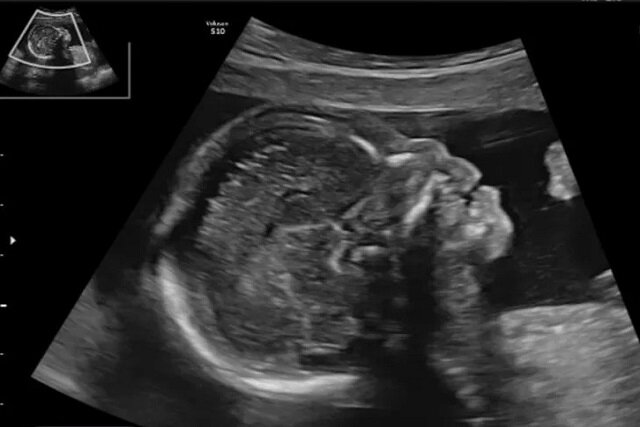

در ایران نیز با توجه به تنوع قومی و ویژگیهای ژنتیکی گوناگون، اندازه و رشد استخوان بینی ممکن است با میانگینهای جهانی تفاوت داشته باشد. به همین دلیل بررسی وضعیت این استخوان در جنینهای ایرانی در سهماهههای مختلف بارداری میتواند به بهبود غربالگری و کاهش نتایج اشتباه در تشخیص کمک کند. اهمیت این بررسی زمانی دوچندان میشود که بدانیم سونوگرافی یکی از کمخطرترین و در دسترسترین ابزارهای بررسی سلامت جنین است.

در راستای مطالعه بیشتر این موضوع، میترا افتخار یزدی، دانشیار گروه زنان و مامایی دانشکده پزشکی دانشگاه علوم پزشکی سبزوار، به همراه پنج همکار خود، پژوهشی را برای بررسی ارتباط اندازه استخوان بینی جنین با بروز سندرم داون انجام دادهاند. این مطالعه با هدف یافتن رابطه میان مشاهده یا عدم مشاهده استخوان بینی در دو مرحله از بارداری یعنی سهماهه اول و دوم طراحی شده است تا مشخص شود آیا این شاخص میتواند بهتنهایی معیار مناسبی برای تشخیص زودهنگام ناهنجاریهای ژنتیکی باشد یا خیر.

در این پژوهش، ۲۶۵ خانم باردار مراجعهکننده به کلینیک پریناتولوژی دانشگاه علوم پزشکی سبزوار مورد بررسی قرار گرفتند. در این مطالعه، جنینهایی که در سونوگرافی سهماهه اول استخوان بینی آنها مشاهده نمیشد یا در سهماهه دوم دچار کوتاهی غیرطبیعی این استخوان بودند، وارد تحقیق شدند. دادههای استخراجشده از پرونده بیماران با استفاده از نرمافزار آماری مخصوص تحلیل شد تا ارتباط میان اندازه استخوان بینی و نتایج ژنتیکی مشخص شود.